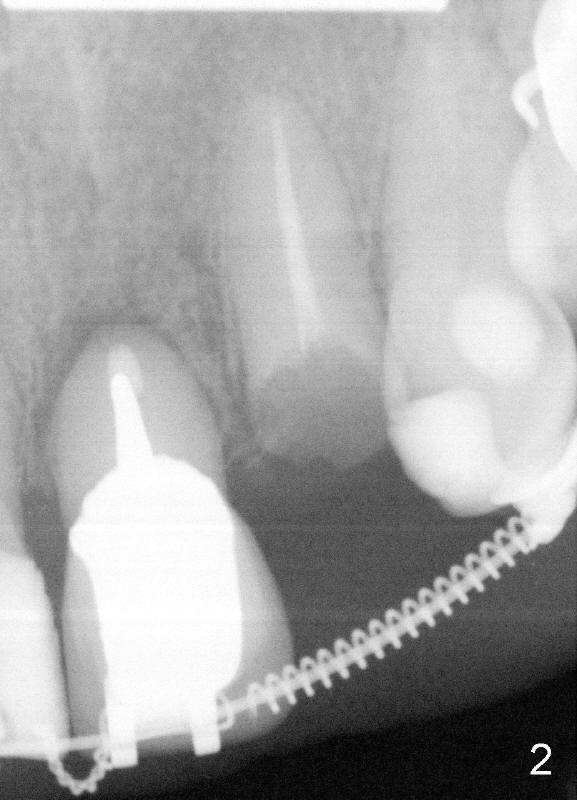

Fig.1 show the sagittal section of the upper left lateral incisor prior to orthodontic treatment. A 3.5x14mm implant is planned to be placed (bone level). Five months of orthodontic treatment results in increased mesiodistal width of the lateral (Fig.2,3), approximately 7 mm, equivalent to that of the #7. A 4x20 mm implant (tissue level) is planned (Fig.3).